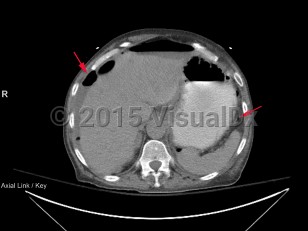

Bowel perforation

Causes of perforation include peptic ulcer disease (mostly duodenal), small and large bowel malignancies with tissue invasion, acute diverticulitis, acute appendicitis in the elderly population, inflammatory bowel disease (Crohn disease, ulcerative colitis), trauma, consequence of ischemic injury, and ingestion of foreign bodies (including fish or poultry bones), or it may occur as a complication of endoscopic procedures.